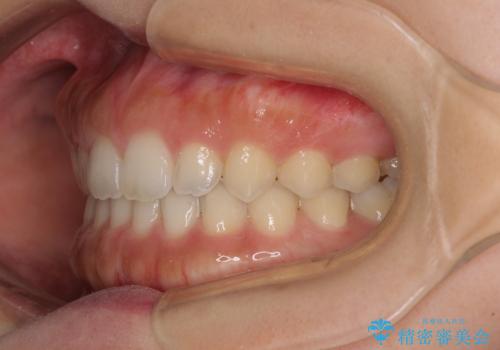

気になる隙間の再矯正 前歯をインビザライン・ライトで改善

- 後戻りによる上下前歯の隙間を気にして来院された患者様です。

歯列不正はそれほど大きくなかったため、インビザライン・ライトを用いて矯正治療を行うこととしました。

無理のないペースで治療を進め、9ヶ月で終えることができました。